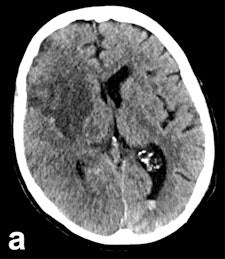

In large clinical studies, thrombectomy has been used mainly in patients whose CTs show a lower degree of severity, normally assessed using the Alberta Stroke Program Early CT Score (ASPECTS). In most of the successful studies, including ESCAPE, SWIFT PRIME, and REVASCAT, the ASPECTS must be no worse than six or seven points out of 10.

ASPECTS scoring is standard in patients who undergo CT for a recent stroke. "Doing the scores manually requires a high degree of experience, and is prone to error," Herweh said, adding that this problem can be solved by using software to calculate the scores. "It's more objective, and may be better than radiologists at evaluating patients' prognoses."

The Brainomix eASPECTS software, which has been around for some time now, is increasingly proving its value in clinical studies.

An initial validation study of 34 patients by the Heidelberg group showed that software evaluation of CT images was better than assessments by radiologists with limited training, and performed to the same level as experts. Furthermore, a U.K. study of 132 patients showed the software was at least equal to neuroradiologists, he explained.

It works from a technical viewpoint, but the key clinical question is whether this method is better than, or as good as, experts at predicting which patients have a poor prognosis. Therefore, Herweh and his colleagues carried out a third study of 212 recent stroke patients, using three experts and the software to calculate the ASPECTS retrospectively. The result was then correlated with the patients' actual clinical progress.

"What we've shown is that the software reliably predicts a poor prognosis following thrombectomy," he stated.

A low eASPECTS has a statistically significant correlation to such a prognosis. Among experts, however, this correlation was statistically significant in only one out of three cases. In other words, software-based scoring could be more objective and clinically conclusive than manual scoring by experts.